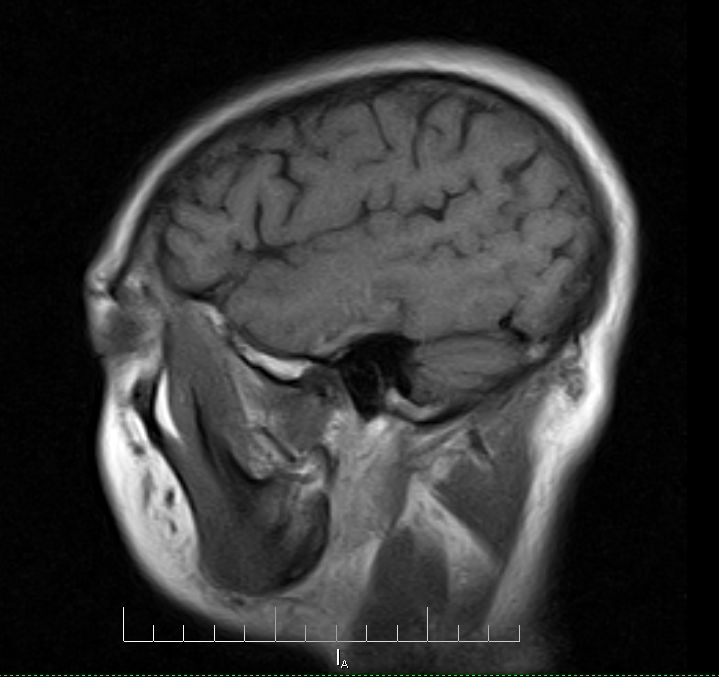

标题: MRI2379:30岁,男,癫痫10年,请各位看一下;CT示:左颞叶钙 [打印本页]

标题: MRI2379:30岁,男,癫痫10年,请各位看一下;CT示:左颞叶钙

左颞叶区见不规则点状混杂信号影

考虑血管畸形

支持2楼 左颞叶区见不规则点状混杂信号影,考虑动静脉畸形。

考虑左侧颞叶脑血管畸形(avm)。

考虑左侧颞叶脑血管畸形(avm)。----t1低等高混杂信号,t2等高信号周边较多流空血管影[冠状位明显],mra左侧大脑中动脉受压,远侧聚集.